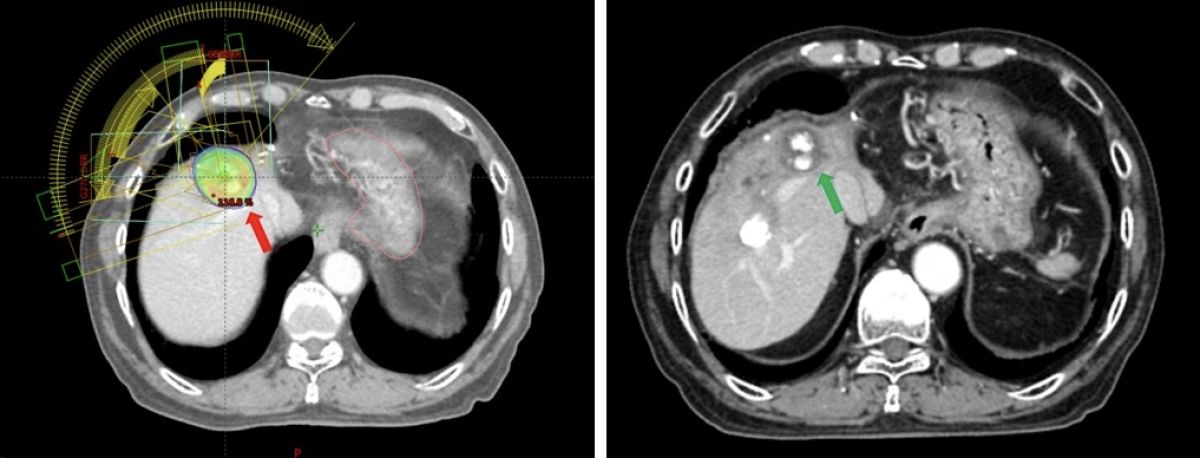

▲澄清醫院中港分院放射腫瘤科主任許維中表示,肝癌的復發是難以預測的,但目前追殺肝癌的方法有很多種,最重要是維持病人的肝臟機能。(圖/澄清醫院提供)